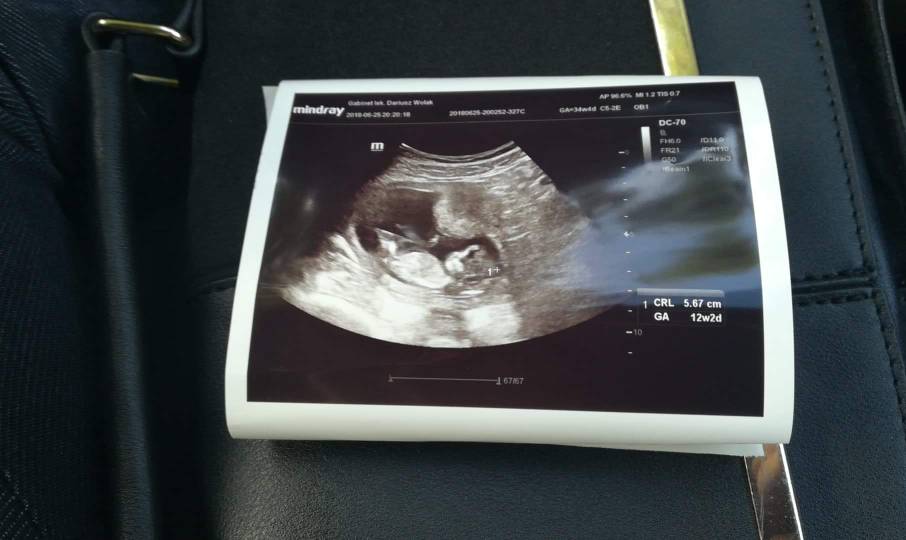

Już po wizycie[emoji7]wszystko w porządku dzidziol ma prawie 6cm nosek rączki nóżki przezierność karkowa też ok. Jestem szczęśliwa [emoji3][emoji3]na bóle brzucha i kłucia mówił że mogę nospe dlatego też ja zakupiłam[emoji6]Zobacz załącznik 870846

Gratuluję [emoji173] cudowne zdjęcie [emoji7]